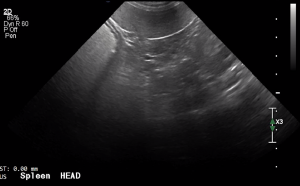

SIMON Ultrasound Database

This ultrasound database is a free resource for students and doctors!

Our collection includes videos of dogs, cats, horses, cows, humans, and many other species!